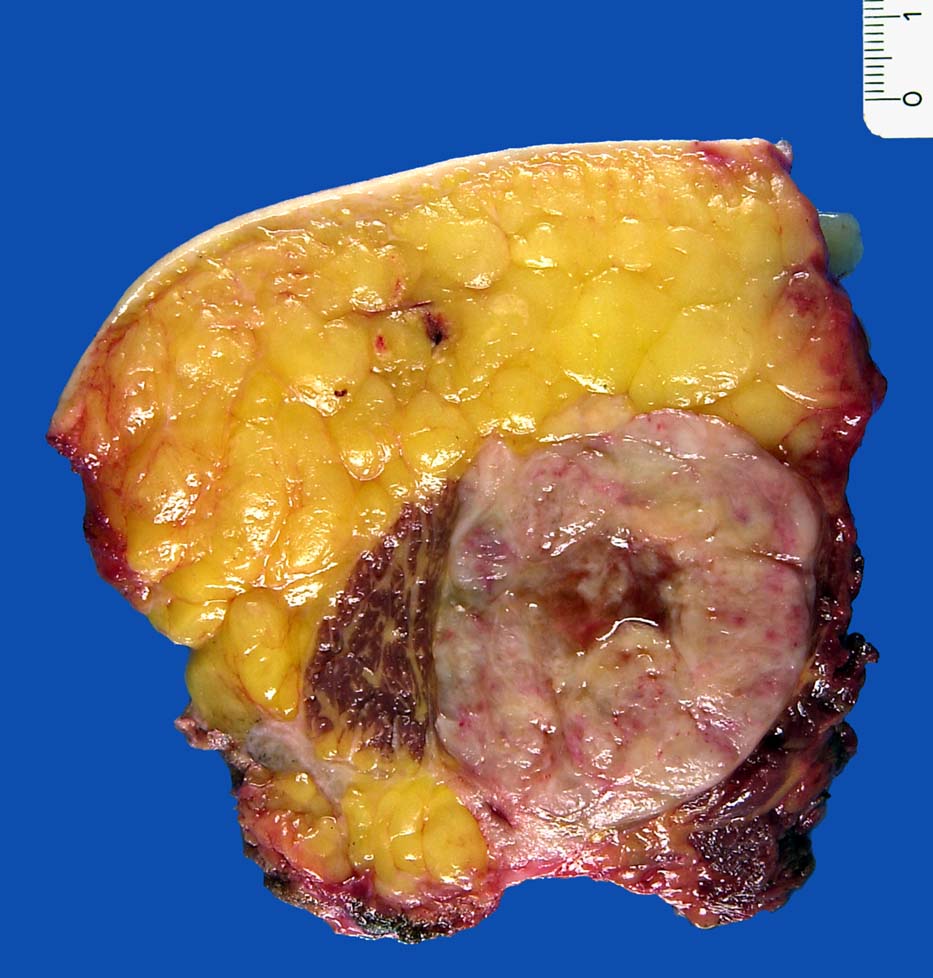

Basel 1MA/ Myxoides Liposarkom

Myxoides Liposarkom

• Am rechten Rand des Präparates komprimierte Skelettmuskulatur.

• Links daran angrenzender scharf begrenzter Tumor mit reichlich myxoidem Stroma.

• Zahlreiche, überwiegend univakuoläre Lipoblasten. Zellkern durch die Lipidvakuole komprimiert und zur Seite verdrängt.

• Zahlreiche krähenfussartig verzweigte Kapillaren.

• Die rundzelligen Anteile erscheinen in der Übersicht aufgrund des Zellreichtums dunkler. Sie bestehen aus dicht gelagerten zytoplasmaarmen Tumorzellen mit vesikulären runden Kernen und einem prominenten Nukleolus.